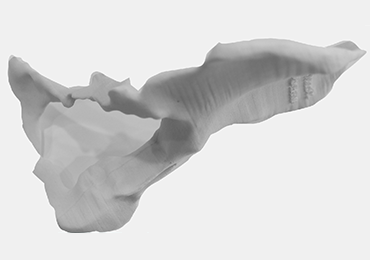

Step 2: The bone model is printed.

Step 3: The implant model is printed.

FINAL PRODUCT: CUSTOM MADE ACETEBULAR REVISION IMPLANT